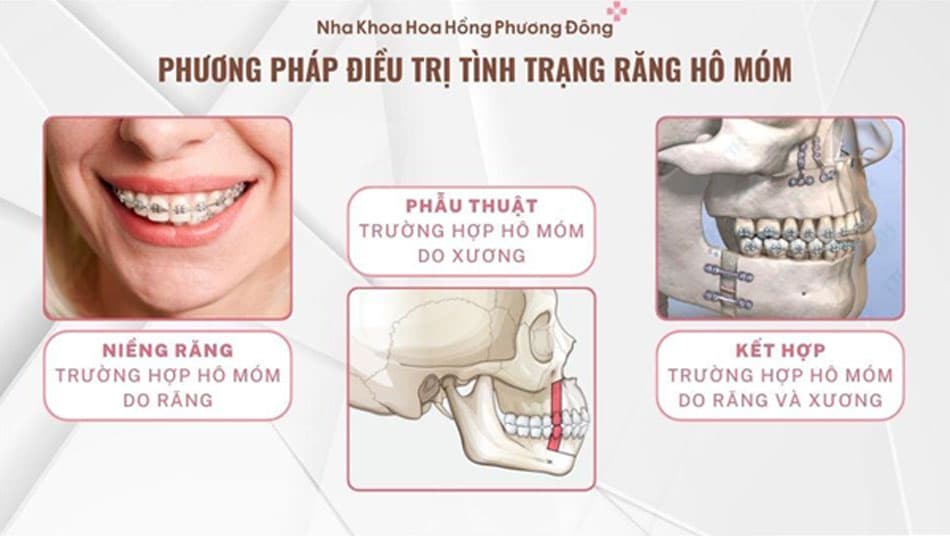

Nên niềng răng hay phẫu thuật khi gặp tình trạng hô móm?

Việc điều trị hô móm cần dựa vào nguyên nhân và mức độ sai lệch của từng trường hợp. Bác sĩ sẽ tiến hành chụp X-Ray để xác định phương án điều trị hiệu quả. Cụ thể:

Hô móm do răng: Nếu nguyên nhân là do răng mọc lệch, niềng răng là giải pháp lý tưởng nhất. Bác sĩ sẽ sử dụng các khí cụ chỉnh nha để điều chỉnh răng về đúng vị trí, cải thiện thẩm mỹ và khớp cắn. Thời gian niềng răng thường dao động từ 1-3 năm, tùy thuộc vào tình trạng cụ thể của từng người.

Hô móm do xương hàm: Trường hợp này xảy ra khi xương hàm phát triển không cân đối, gây sai lệch khớp cắn. Phẫu thuật chỉnh hình hàm là phương pháp hiệu quả nhất để điều chỉnh cấu trúc xương, giúp cải thiện thẩm mỹ và chức năng nhai.

Hô móm do cả răng và xương: Với tình trạng này, bác sĩ sẽ kết hợp niềng răng và phẫu thuật chỉnh hình hàm. Sau khi phẫu thuật, niềng răng là bước quan trọng để ổn định vị trí răng, tránh các vấn đề như răng di chuyển sai lệch hoặc nghiêng vào các khoảng trống giữa răng sau phẫu thuật. Sự kết hợp này đảm bảo kết quả thẩm mỹ và chức năng lâu dài.